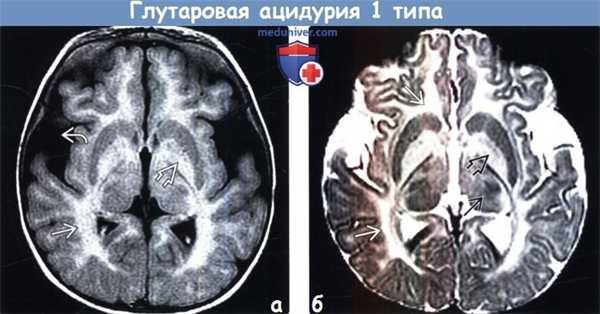

(а) МРТ, Т2-ВИ, аксиальный срез: определяется легкое расширение сильвиевых борозд и ранние изменения сигнала со стороны базальных ганглиев BE и таламусов, имеющих пестрый внешний вид. Наличие макрокрании -дополнительный признак, помогающий в постановке диагноза, когда другие изменения при глутаровой ацидурии 1 типа (ГА1) выражены минимально.

(б) МРТ-исследование ребенка в возрасте 21 месяца через длительный промежуток времени после разрешения метаболического криза, Т2-ВИ, аксиальный срез: выявляется атрофия легкой степени выраженности, глиоз базальных ганглиев, также сохраняется расширение сильвиевых борозд.